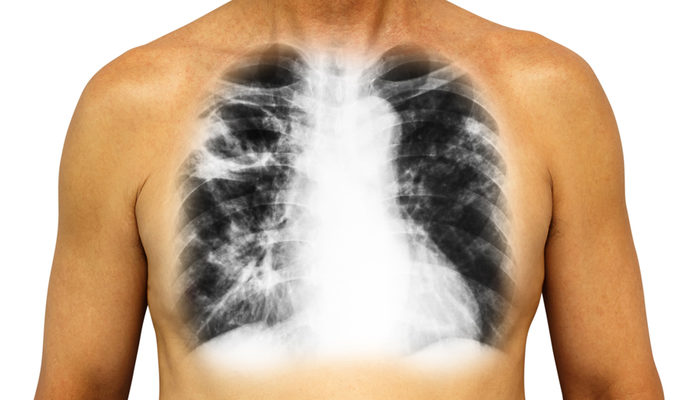

KOAH nedir? KOAH nedenleri nelerdir? KOAH tedavisi nasıl olur? KOAH öldürüyor!

KOAH, dünyada her sene sıradan 4 milyon, Türkiye ’de ise 50 bin kişinin hayatını kaybetmesine neden oluyor. Ülkemizde 40 yaş üstündeki her 10 kişiden birinin çaba ettiği KOAH, Türkiye ’de yaşanan ölümlerin nedenleri arasında dolaşım sistemi hastalıkları, yürek hastalıkları ve tümörlerden daha sonra dördüncü sırada yer alıyor. Central Hospital ’dan...